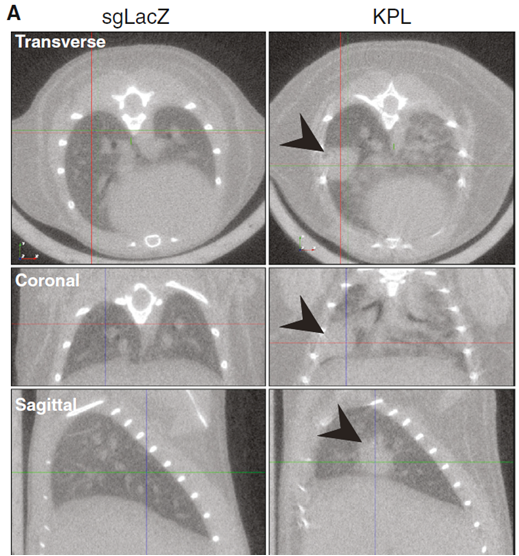

AAV介导的CRISPR-Cas9系统实现对小鼠基因组编辑和癌症建模

载体:AAV9-KPL(sgKras-sgP53-sgLkb1);

实验动物:Cre依赖Cas9小鼠

注射方式和剂量:鼻腔和气管注射。每只小鼠注入病毒总量1x1011 GCs. Vol: 鼻腔 50ul,气管70ul;

启动子:U6,EFS;

实验方法和结果:通过将携带肺靶向作用及调控元件的AAV病毒(AAV9-KPL和AAV9-sgLacZ)导入小鼠体内,实现对肺腺癌常见易感基因(p53、Lkb1)功能缺失或突变,导致腺癌病理中产生肉眼可见的肿瘤。注射后3周、肺部μCT成像。

图2. 病毒介导的调控元件诱导肺部肿瘤的形成[4]